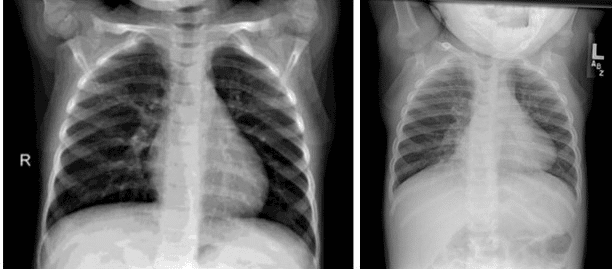

Chest radiograph of an infant showing bilateral pulmonary hyperinflation in RSV

Chest radiograph of a healthy child vs a child with bronchiolitis due to RSV

Bilateral patchy consolidation in a predominantly perihilar distribution extending to the bases. Left lower lobe and right middle lobe confluent consolidation. (Features of RSV pneumonitis in a 9-month-old infant)

X-ray of a child with RSV showing the typical bilateral perihilar fullness of bronchiolitis